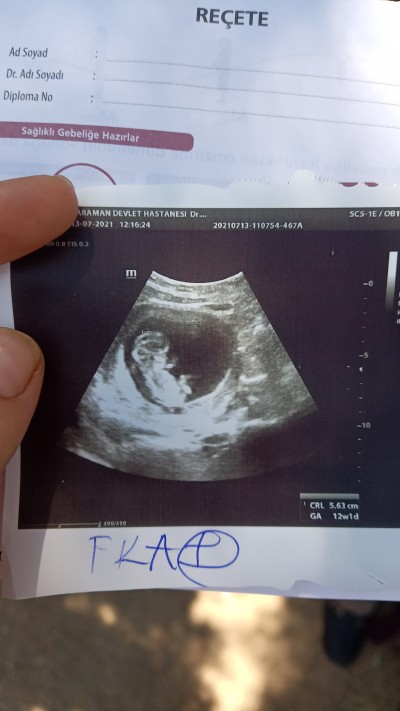

merhabalar doktorun bakmaya zamanı yoktu cinsiyeti es geçti icinizden geçenler nedir

Gebelik haftası 12+1

Nub çok belli değil ama kız sanki

Benimde kesen böyle yuvarlak sanırım kız:) bende bilmiyorum ama

Cinsiyeti analmadım. Ama keyifli olacak ellere bak kafasının altına koymuş minnoş

(7 puan)

Eveeet baya keyifci olacak ultrasonu tutar tutmaz bu pozu verdi hemen